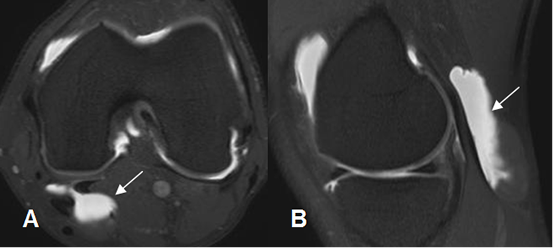

En la RM se aprecia como lesión quística posterior. Puede presentar signos de sinovitis o cuerpos libres en su interior. (Fig 176 a 179).

Fig 177. Quiste de Baker.

A: ArtroRM axial en STIR y B: ArtroRM sagital en STIR. Presencia de contraste en el interior de un quiste de Baker, por su comunicación con la cavidad articular.